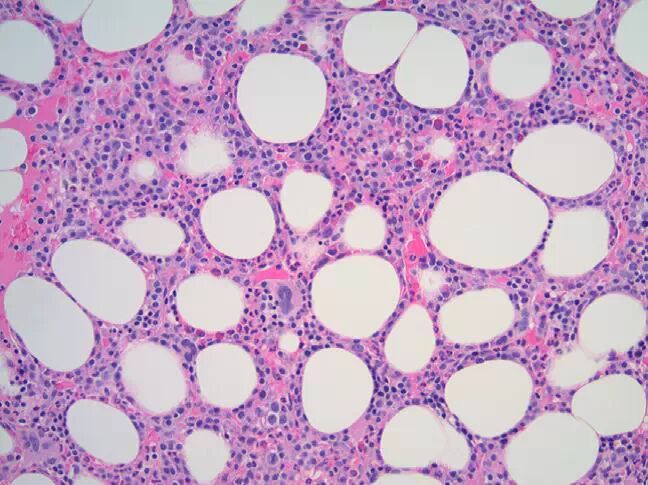

一名58岁女性发现贫血,血红蛋白7g/dL(正常为11.5-15.5)。患者做了结肠镜筛查并遵嘱服用铁剂。此后患者出现了视力模糊,就诊于验光师,发现视网膜出血,因此被介绍至眼科医师处做实验室检查,结果(括号内为参考值)发现血清总蛋白升高至15.8g/dL(6-8.4)、血清IgG为11,316mg/dL(717-1411)、肌酐水平处于1.4mg/dL(0.7-1.4)的交界值、IgA降低至22mg/dL(78-391)、IgM降低至13mg/dL(53-334)。血清钙为8.9mg/dL(8.5-10.5)的正常值。进一步检查,血清蛋白电泳及免疫固定电泳发现血清IgG-κ单克隆蛋白9.16g/dL。血清β2-微球蛋白升高(7mg/dL,正常为0.3-1.9),白蛋白降低(2.4g/dL,正常3.5-5.0),乳酸脱氢酶(lactate dehydrogenase,LDH)位于正常范围(164U/L,正常为100-220)。全血细胞计数见白细胞为3.8×103/μL(正常3.8-11.0),血红蛋白5.7g/dL(正常11.5-15.5),红细胞压积18.8%(正常36.0-46.0%),血小板152×103/μL(正常150-400),外周血中浆细胞4%(见图1)。骨髓穿刺涂片(图2)及粗针活检(图3)浆细胞肿瘤性成分占全部骨髓中细胞成分的70%。粗针穿刺标本中做免疫染色,见CD138(syndecan-1)和κ轻链阳性、而CD79a(mb-1; Ig-α)、CD56(NCAM-1)、cyclinD1、ι轻链阴性的浆细胞数量显著增加。细胞遗传学见正常女性核型。骨髓标本分裂间期荧光原位杂交(fluorescence in situ hybridization,FISH)分析见13号染色体单体(图4)及t(4;14)IgH/FGFR3融合(图5)。骨骼检查见T8椎体部分压缩性骨折。 根据Durie-Salmon分期10和国际分期系统(International Staging System,ISS)11,该患者为III期、高危型骨髓瘤。患者接受了浓集红细胞输注。硼替佐米(bortezomib)、来那度胺(revlimid)、地塞米松方案(VRD)的治疗中,出现了中到重度的疲倦、腹泻、神经病变、味觉障碍及体重减轻等并发症。治疗后,血清单克隆异常蛋白降至0.16g/dL,尿中未测出单克隆蛋白。五个周期的治疗后,达到了极好的部分缓解。 这一高危型多发性骨髓瘤患者的处理过程中,出现了几个问题: 1、含硼替佐米方案的治疗是否为克服其高危型疾病所必需? 2、如果患者最初未达到完全缓解,是否需要更改初始的治疗方案? 3、自体干细胞移植(autologous stem cell transplantation,ASCT)或序贯自体干细胞移植(序贯移植或二次移植,是指包括使用两个周期的大剂量苯丙氨酸氮芥以及首次移植后数月内第二次干细胞输注)是否有助于改善其中位生存期、该方案是当前的标准方案吗? 4、对这一高危型疾病患者,尽管异体骨髓移植具有较高的治疗相关死亡率,但是否也可以考虑? 5、恰当的治疗终点是何时:完全缓解?无进展生存(progression-free survival,PFS)?还是到中位生存期? 6、最后,该患者最恰当的维持治疗是什么? 图1.外周血涂片(×50,瑞氏染色)见正常红细胞性贫血,伴红细胞形成显著缗钱状,可见浆细胞。 图2.骨髓抽吸涂片(×50,瑞氏染色)可见非典型浆细胞显著增加,伴大小不等的红细胞,偶见伴显著核仁或双核的不成熟型(图中未示)。 图3.骨髓粗针活检(×20,苏木素伊红染色)见老化的细胞数量增加(约60%)、伴造血细胞三系均成熟减少,伴核仁的非典型性及未成熟性浆细胞显著增加、约占骨髓细胞数量的70%。免疫组化染色(图中未示)见浆细胞CD138和κ轻链阳性,而ι轻链、CD56、CD79a、cyclinD1阴性。 图4.分裂间期荧光原位杂交见一个细胞中有两个来自正常着丝粒的蓝色信号、一个来自特异性位点13q14(Rb1)探针的红色信号,一个来自13q34(LAMP1)探针的绿色信号。这一信号模式代表13号染色体三体。 图5. 分裂间期荧光原位杂交见一个细胞具有来自特异性位点14q32(IgH)探针的绿色信号、来自4p16(FGFR3)探针的橙色信号以及两个信号接近后的融合。这一信号模式代表t(4;14)(p16;q32)。 |